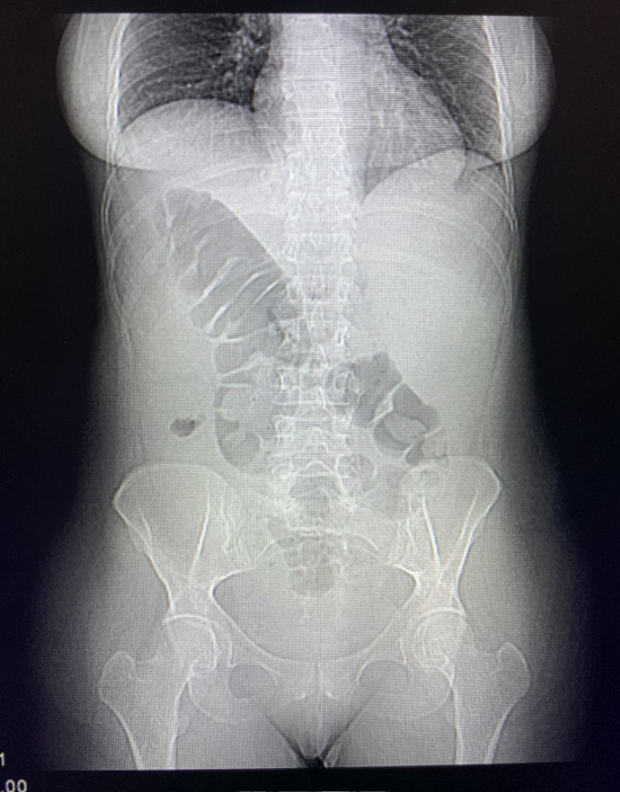

Radiografía Tórax: sin patología aguda en parénquima ni en pleura pulmonares.

Radiografía Abdomen: Asas de delgado en marco colónico derecho. Gas en marco colónico izquierdo, Heces en ampolla rectal, sin niveles hidroaéreos (no describen anormalidades).